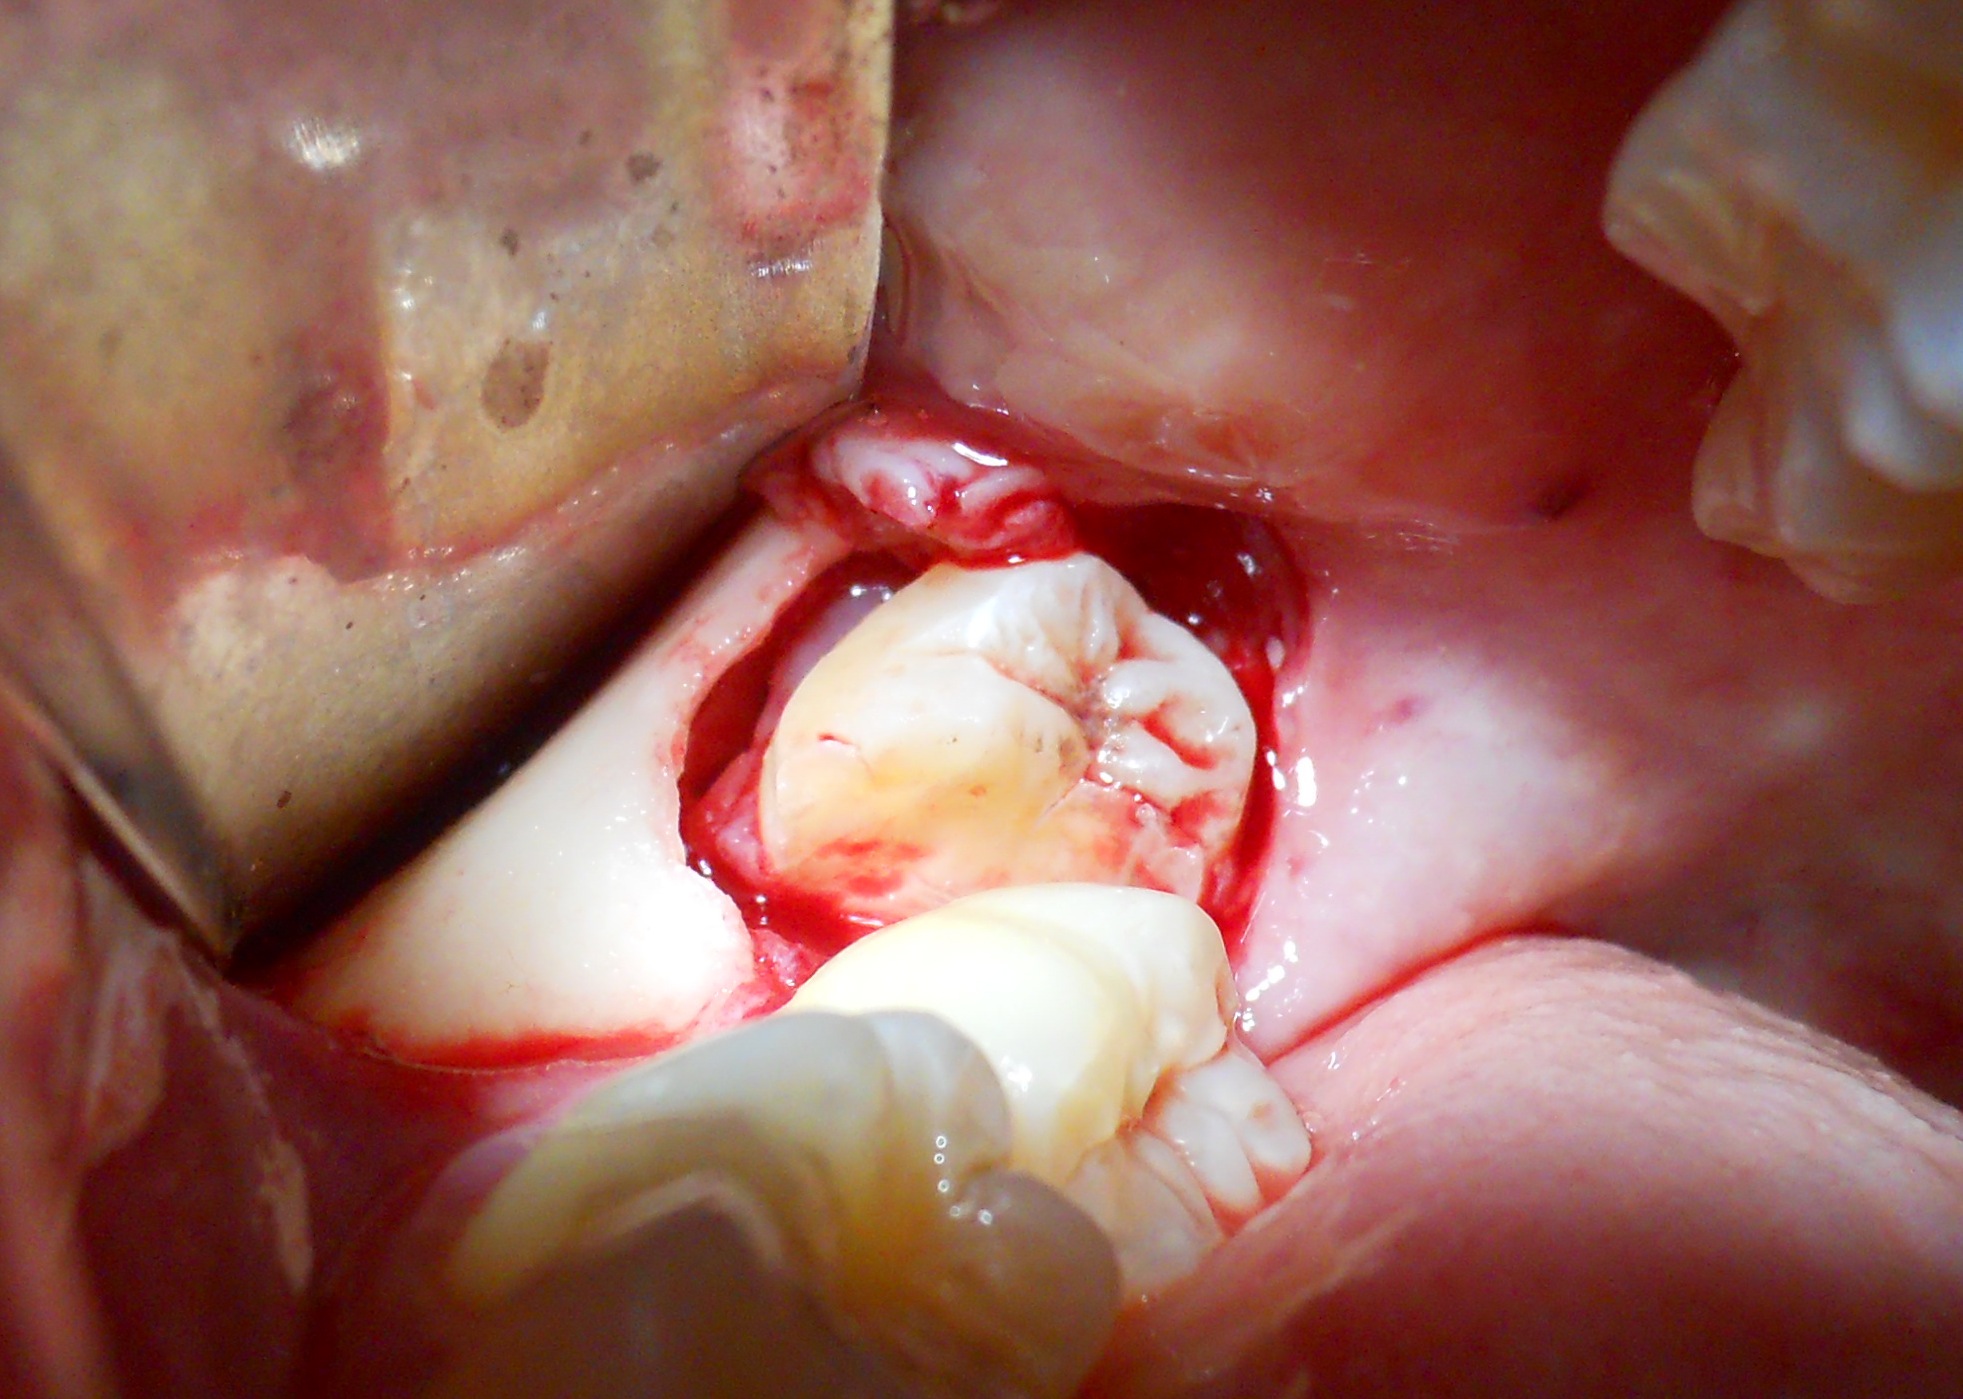

Presentazione del Caso:

Il paziente di presenta alla mia attenzione lamentando continua fuori uscita di liquido purulento in corrispondenza del IV quadrante.

Dopo test di vitalità negativo degli elementi coinvolti (44 e 45) e dopo presa visione della panoramica si decide di intervenire effettuando un'enucleazione della cisti odontogena.

A seguito dell'intervento si valuta la vitalità di 43 che rimane positiva.E' da notare a distanza di 2 mesi parestesia del labbro inf. dx. poi scomparsa al terzo mese dall'intervento